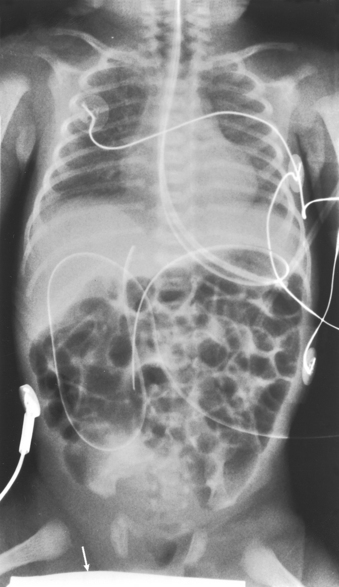

Patients who are in intensive care units or orthopedic beds because of fractures may be attached to various devices, wires, and tubing. These objects may be in the direct path of the x-ray beam and consequently produce artifacts on the image. Experienced radiographers know which of these objects can be moved out of the x-ray beam. When devices such as fracture frames cannot be moved, it may be necessary to angle the central ray or adjust the IR to obtain the best radiograph possible. In many instances, the objects have to be radiographed along with the body part (Fig. 28-9). The radiographer must exercise caution when handling any of these devices and should never remove traction devices without the assistance of a physician.

Structures shown: This projection shows the pelvis, including the following: both hip bones; the sacrum and coccyx; and the head, neck, trochanters, and proximal portion of the femora (Fig. 28-19).

Structures shown: The distal two thirds of the femur, including the knee joint, are shown (Fig. 28-21).